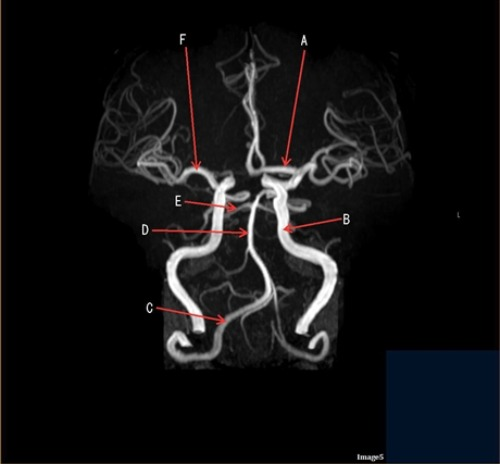

Letter F in Image 5 is pointing to:

E. Middle cerebral artery

Letter C in Image 5 is pointing to:

A. Vertebral artery

Letter D in Image 5 is pointing to:

C. Basilar artery

Letter A in Image 5 is pointing to:

A. Anterior cerebral artery

Letter E in Image 5 is pointing to:

D. Posterior cerebral artery

Image 5 is an example of an:

D. MRA Circle of Willis

Letter B in Image 5 is pointing to:

B Internal carotid artery